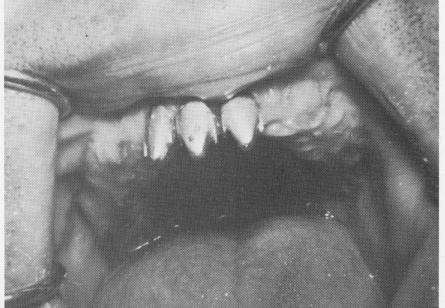

Fig. 4-36. In an attempt to save the loose prosthesis, pir implants were driven through the palatal bar into bone

1 Tripod pin implant through palatal bar in bone to save prosthesis